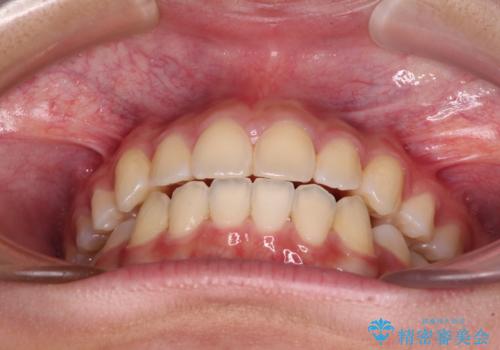

当初は八重歯やデコボコが一番気になっていましたが、抜歯矯正により口元の突出感が改善されるにつれ、口の閉じやすさを実感するようになってきました。

部活動で調整来院に来られないことがしばしばあり、期間は予定よりもかかりましたが、きれいに仕上げることができました。